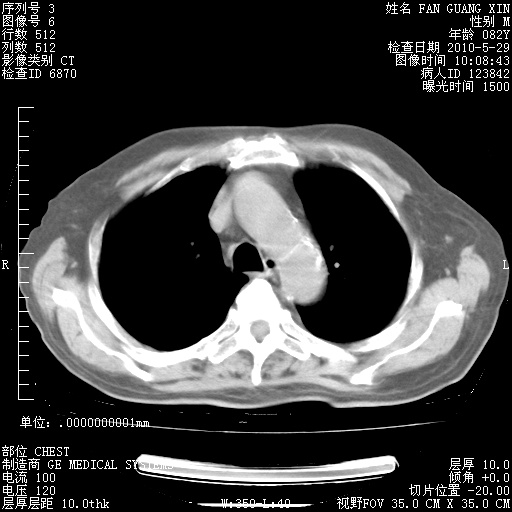

还需要哪些辅助检查?我们医院排除真菌感染没有任何检验方法,胸片好像能够排除肺部真菌感染。

补充:ENA化验全部阴性。免疫五项(IgG、IgA、IgM、C3、C4)只有C4略高。

CD3+ T细胞/淋巴细胞 46% (参考值50.00~84.00%)

CD3+CD4+ T细胞/淋巴细胞 21% (参考值27.00~51.00%)

CD3+CD8+ T细胞/淋巴细胞 25% (参考值15.00~44.00%)

CD3+CD4+ T细胞/CD3+CD8+ T细胞 0.84 (参考值0.71~2.78)

T细胞亚群是治疗5天采血。